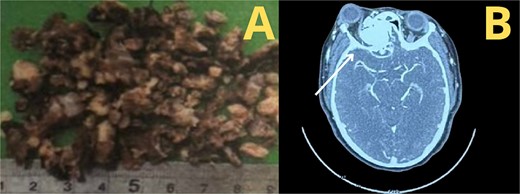

According to the information gathered, the surgeon decided to perform a partial resection of the maxillary neoplasia (Fig. 2). The chosen approach upon evaluation was the Caldwell–Luc procedure, gaining access to the maxillary sinus. Dimensions and anatomic relationships of the mass were established, determining an extension up to the sphenoid bone covering the ipsilateral choana. A predominantly osseous tumor was observed, with a significant contribution of trabecular bone, vascularized, exhibiting a tendency to hemorrhage. Partial resection of the tumor was accomplished, leading to visualization of the peripheral orbit but not decompressing it totally due to hemodynamic instability during intervention. A residual mass was left at the sphenoidal level and cranial base, a future reintervention was considered.

The patient's ocular outcome was favorable, with preserved vision and mild lateral gaze restriction, thanks to the surgical team's focus on preserving orbital structures. This was key to her positive recovery. The diagnosis was JOF, a rare benign tumor common in adolescents, which causes aggressive local growth and carries a recurrence risk. Imaging played a critical role in diagnosis and management.

A second intervention was performed with the Caldwell–Luc approach for complete tumor removal.